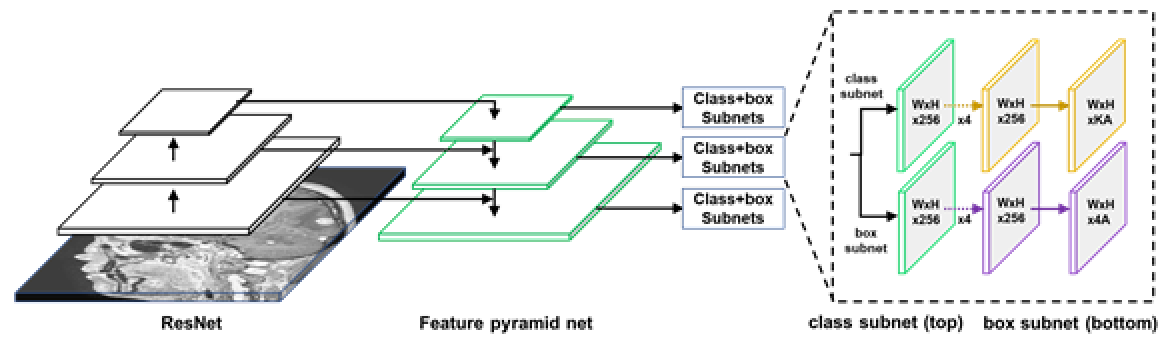

AI 모델 상세 설명서 다운로드 AI 모델 다운로드학습 알고리즘 RetinaNet 및 U-net 기반

RetinaNet과 U-Net을 함께 사용 또는 U-Net만 사용

RetinaNet network 개념도

학습 조건 epoch: 500

batch: 128

optimizer: Adam

loss: categorical cross-entropy, focal-loss

iteration: 4,434